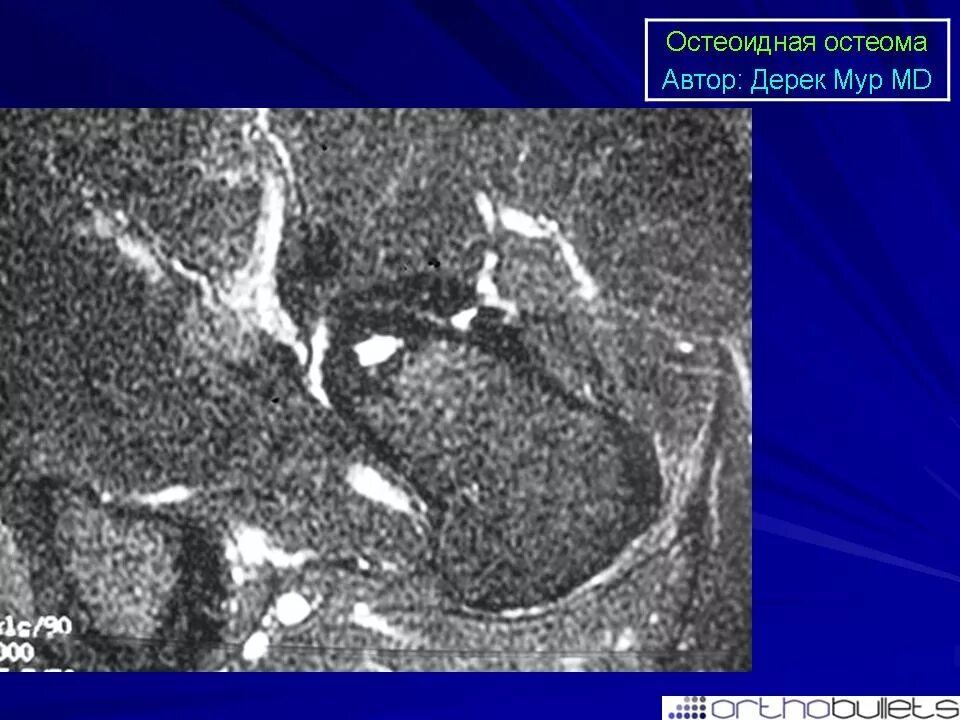

Остеома мрт